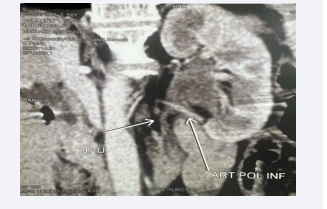

The patient was hospitalized and a contrast-enhanced URO-CT was performed (Figure 1) to determine the cause of the complaints. This examination revealed left pelvicalyceal system dilatation and ipsilateral UPJ obstruction due to a lower pole crossing vessel.

Uro-CT showing crossing vessel responsible of UPJO.

Figure 1: Uro-CT showing crossing vessel responsible of UPJO.